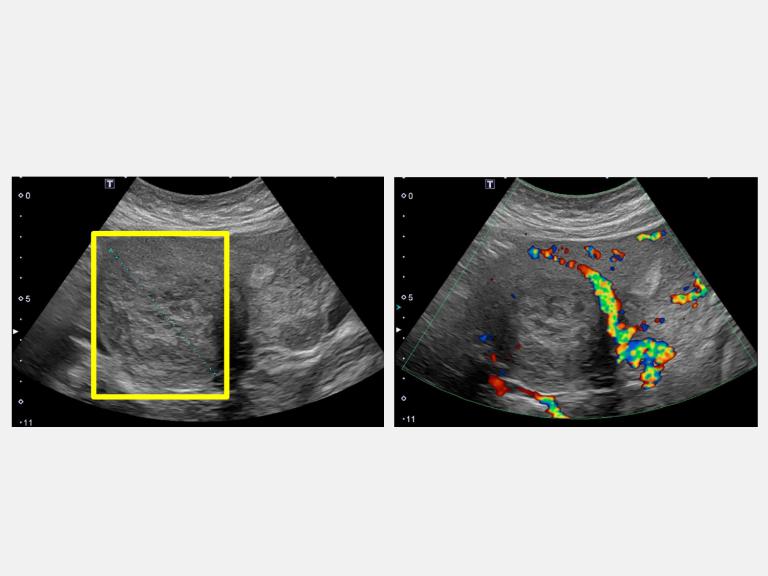

▲超音波顯示病人下腹部悶痛合併壓迫症狀,有7公分肌瘤(左圖方框處)。(圖╱仁愛長庚醫院提供)